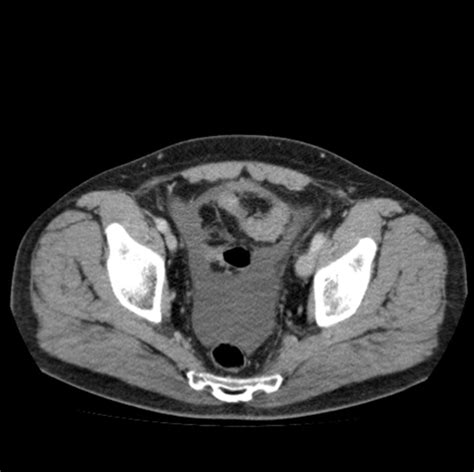

Follikuläres Lymphom: 64-jährige Frau